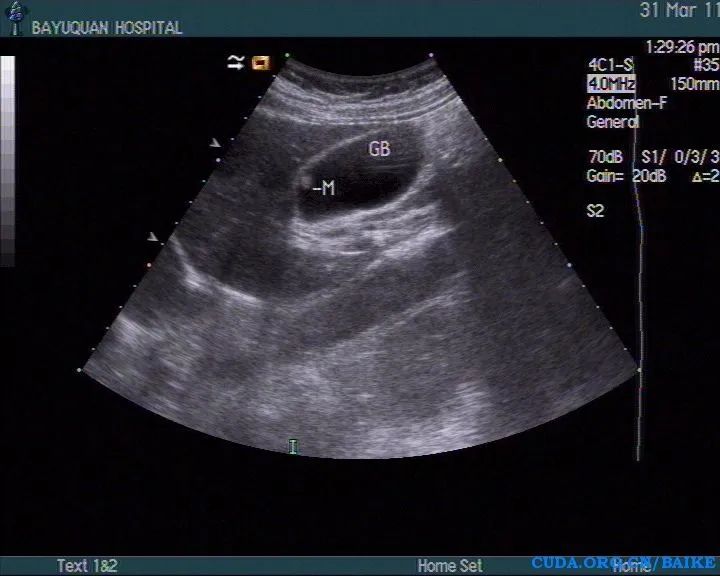

首先我要说,胆囊息肉是B超检查的产物,在没有B超之前,胆囊息肉是个查不出来的,在现在各种影像学检查这么发达的情况下,检查胆囊息肉准确率最高的仍然是是B超。我们知道,胆囊结石的B超表现是:强回声伴声影随体位移动。而胆囊息肉的B超表现呢?大同小异,也是强回声伴声影,区别只是,不随体位移动。也就是说,结石是长在胆囊腔里,息肉是长在胆囊壁上。也就是说:凡是胆囊壁向腔内突出,呈息肉样突起的一类病变都叫胆囊息肉,也叫胆囊隆起样病变,或胆囊息肉样病变。总之,胆囊息肉不是一种病,而是一类病,是一类病的总称。